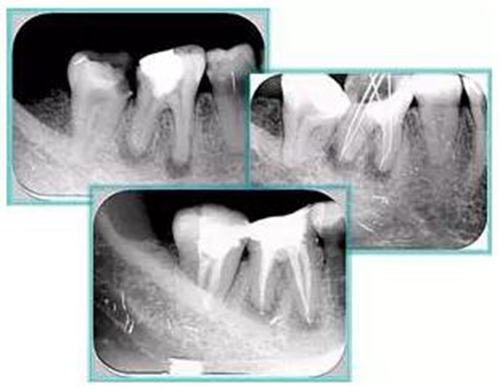

2. X 線片

共有 4 張 X 線片,分別是術(shù)前、診斷絲 、主牙膠尖確認(rèn)、術(shù)后。

( 1 )術(shù)前:術(shù)前 X 線片用來了解牙齒的大概情況。術(shù)前預(yù)期為多根牙時(shí) X 線片應(yīng)偏頭拍攝。

( 2 )診斷絲:根據(jù)術(shù)前 X 線片進(jìn)行開髓、根管的初步預(yù)備后,需要插入診斷絲,用來指示工作器械位置。常用 10 號(hào)或 15 號(hào)擴(kuò)大器作為診斷絲插入牙髓腔。

( 3 )主牙膠尖確認(rèn):通過術(shù)前預(yù)期和診斷絲診斷,明確工作長(zhǎng)度、牙根走向,進(jìn)行根管預(yù)備。之后應(yīng)進(jìn)行主牙膠尖(中銼)確認(rèn),已明確根管是否適合充填。

( 4 )術(shù)后:觀察治療效果。